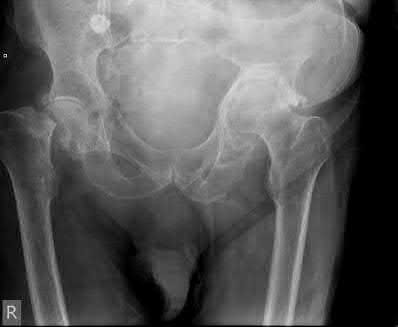

A 12-year-old obese male presents with left groin pain and an altered gait. Based on the presumed diagnosis of slipped capital femoral epiphysis (SCFE) shown in the representative radiograph, which of the following is the primary blood supply to the femoral head that is at highest risk for iatrogenic injury during percutaneous in situ pinning if the pin is placed in the posterosuperior quadrant?

The primary blood supply to the capital femoral epiphysis in children over the age of 3 is the posterosuperior retinacular vessels (lateral epiphyseal artery), which are terminal branches of the medial circumflex femoral artery (MCFA). During in situ pinning for SCFE, placement of the pin in the posterosuperior quadrant of the femoral neck/head places these extracapsular vessels at extreme risk of injury, potentially leading to avascular necrosis (AVN). Pins should ideally be placed in the center-center position to minimize this risk.